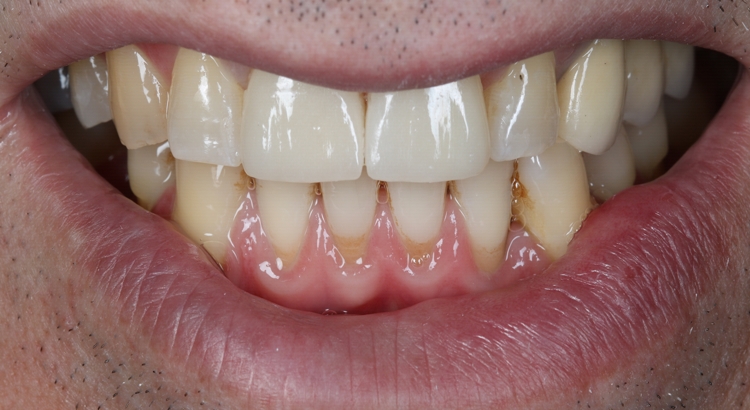

Güvenebileceğiniz Sonuçlar